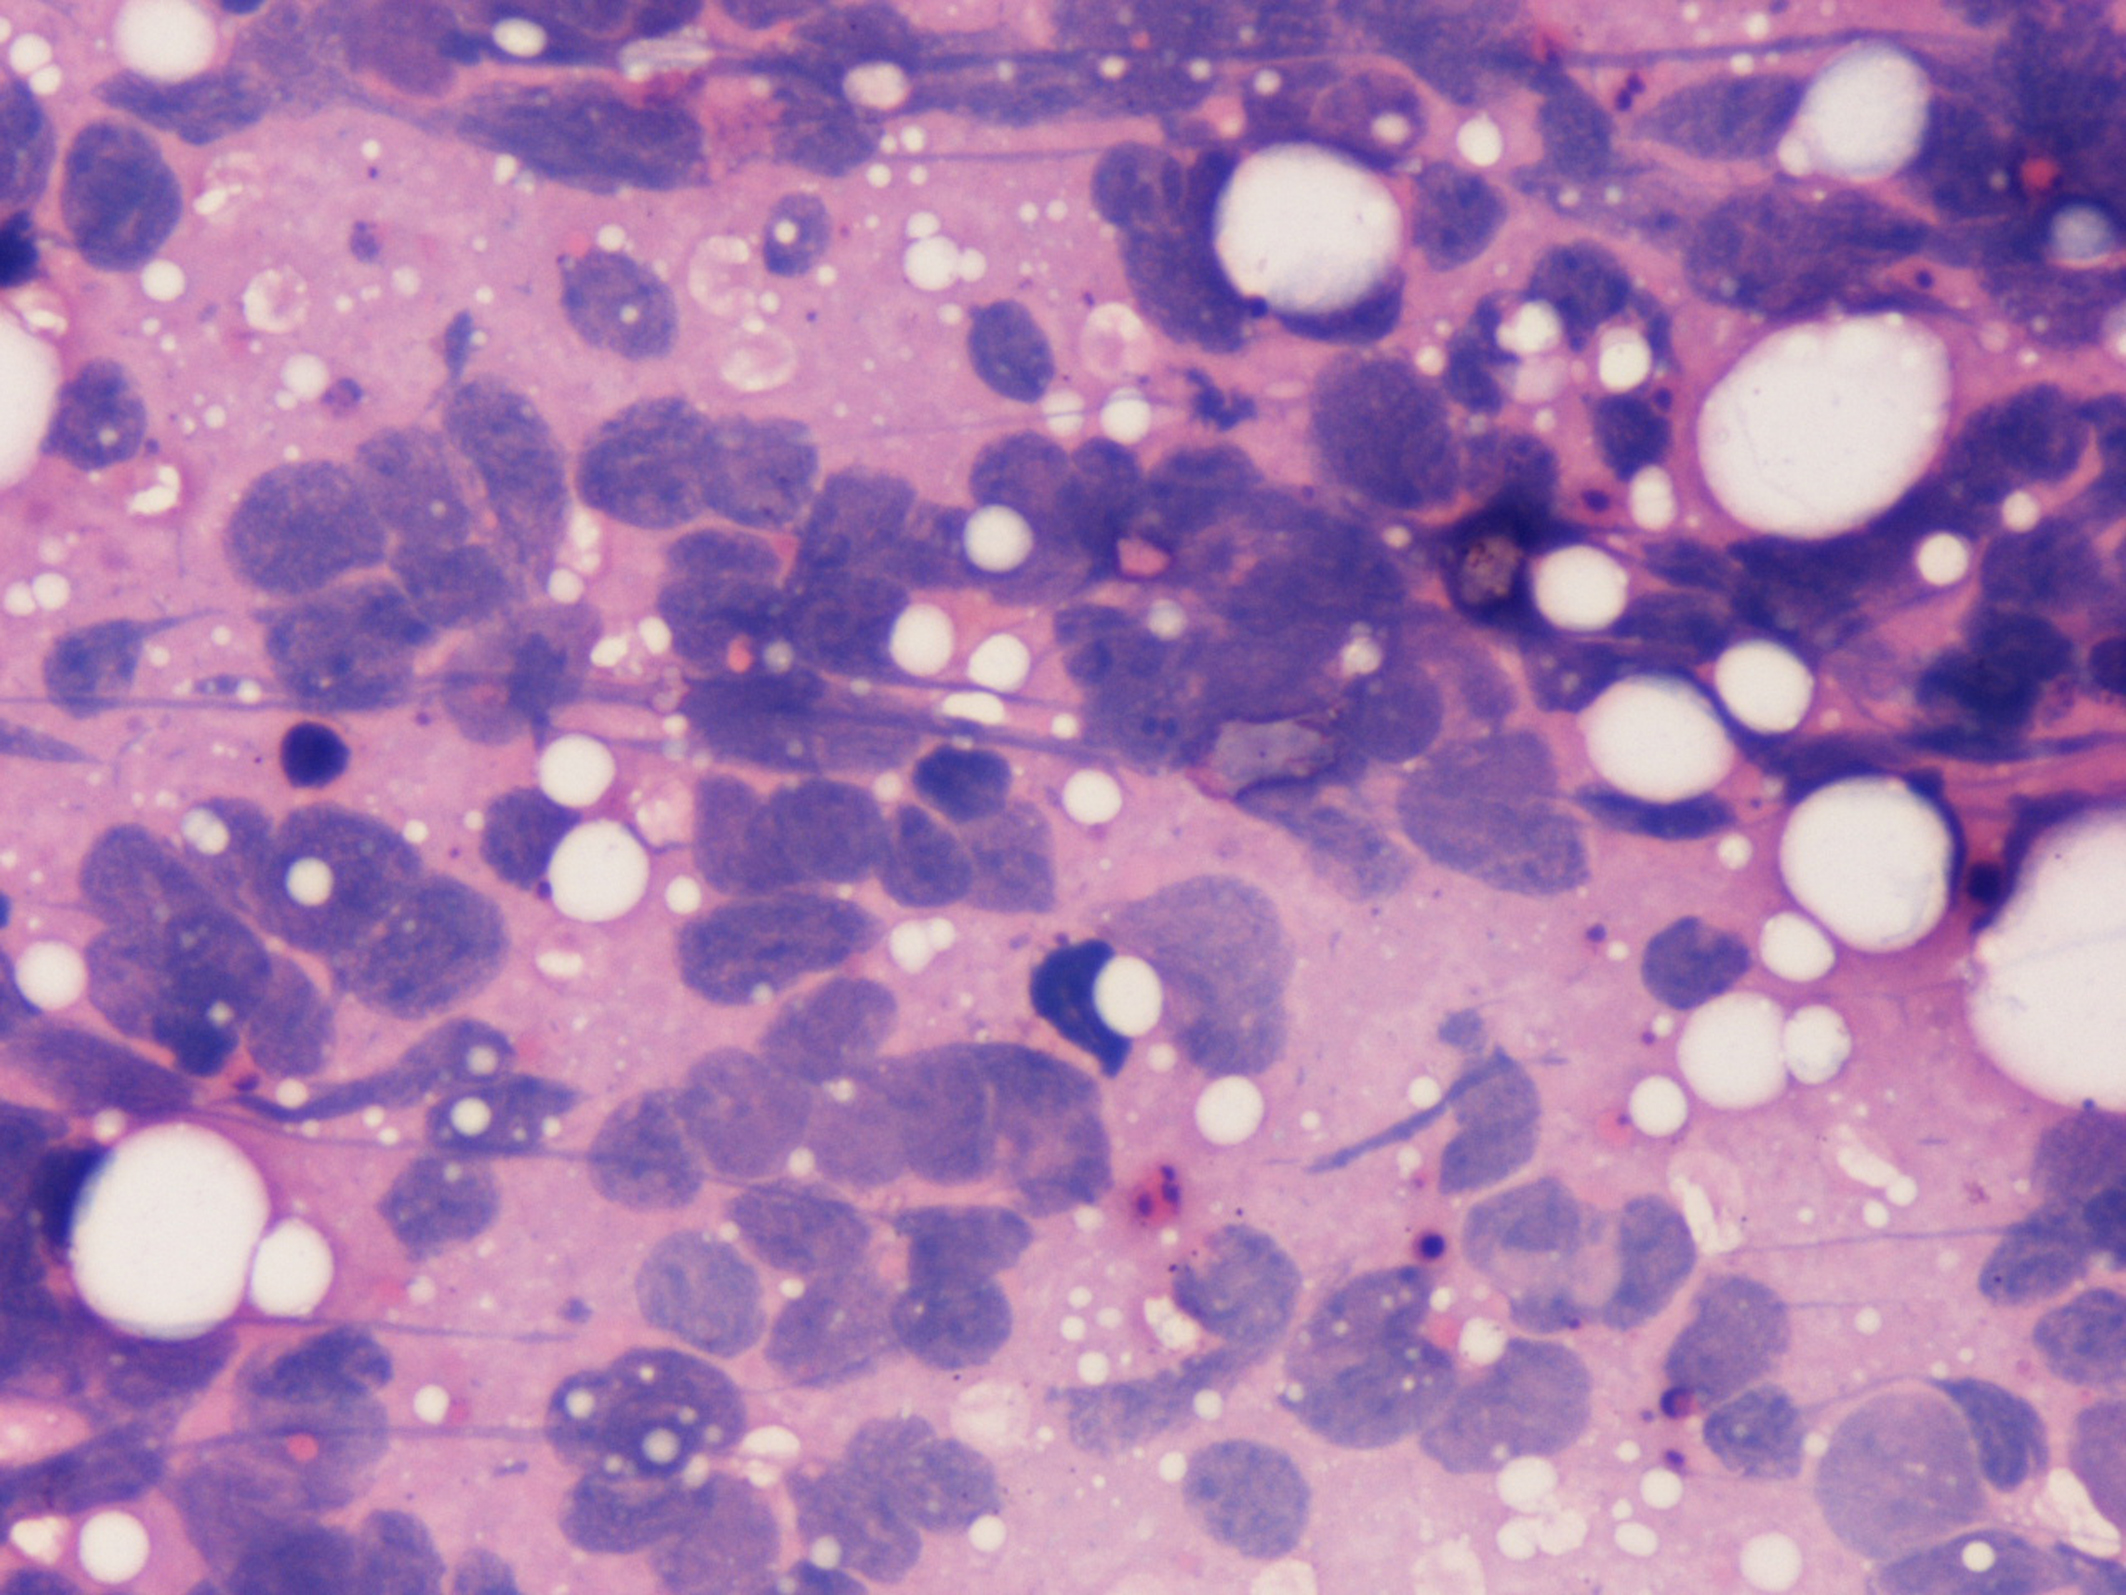

The aspirate from the breast lump was highly cellular with sheets and clusters of cells amid scattered fat vacuoles. Numerous stippled nuclei with marked nuclear streaking and distortion were present. Nuclear moulding and faceting was a notable feature of the tumour cells. No normal ductal cells were seen in the smears.

![]() Click for large image | Figure 3. Aspirate from breast lump showing prominent nuclear moulding and streaking in malignant cells (H&E, ×500). |